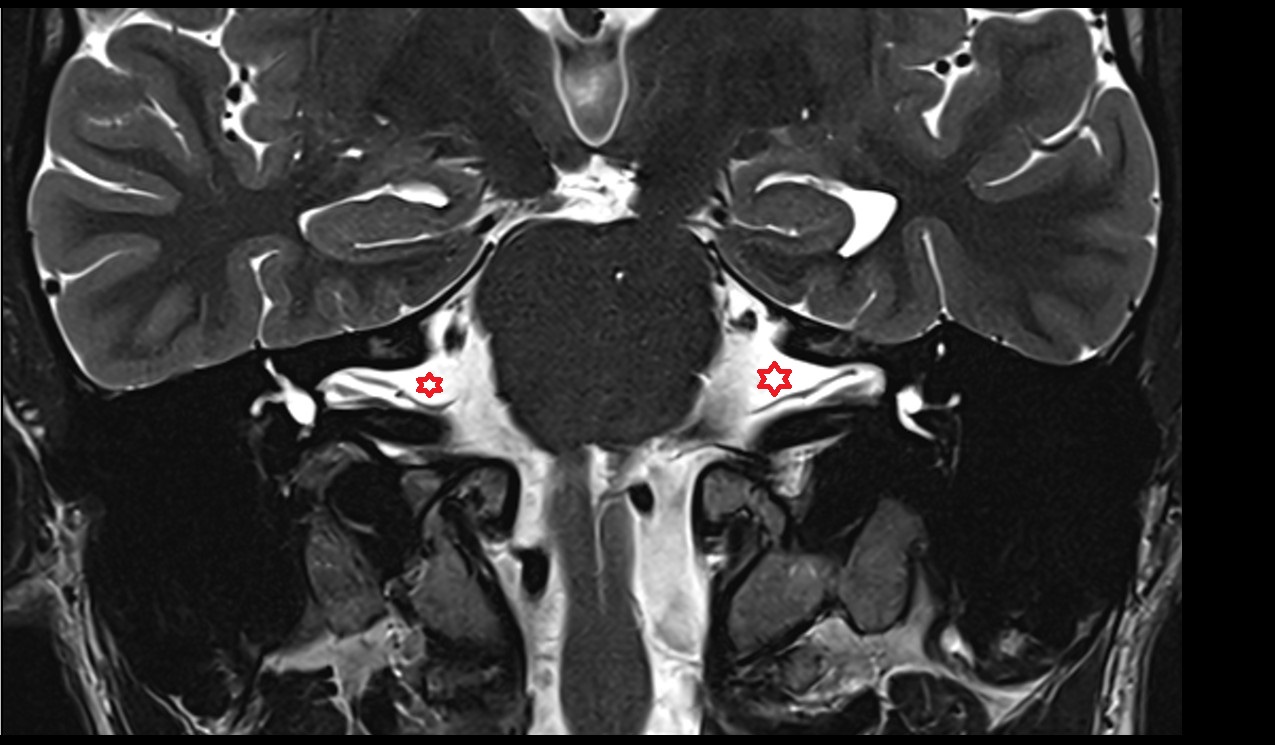

- Body of hippocampus

- Head of hippocampus

- Tail of hippocampus

- Hippocampus